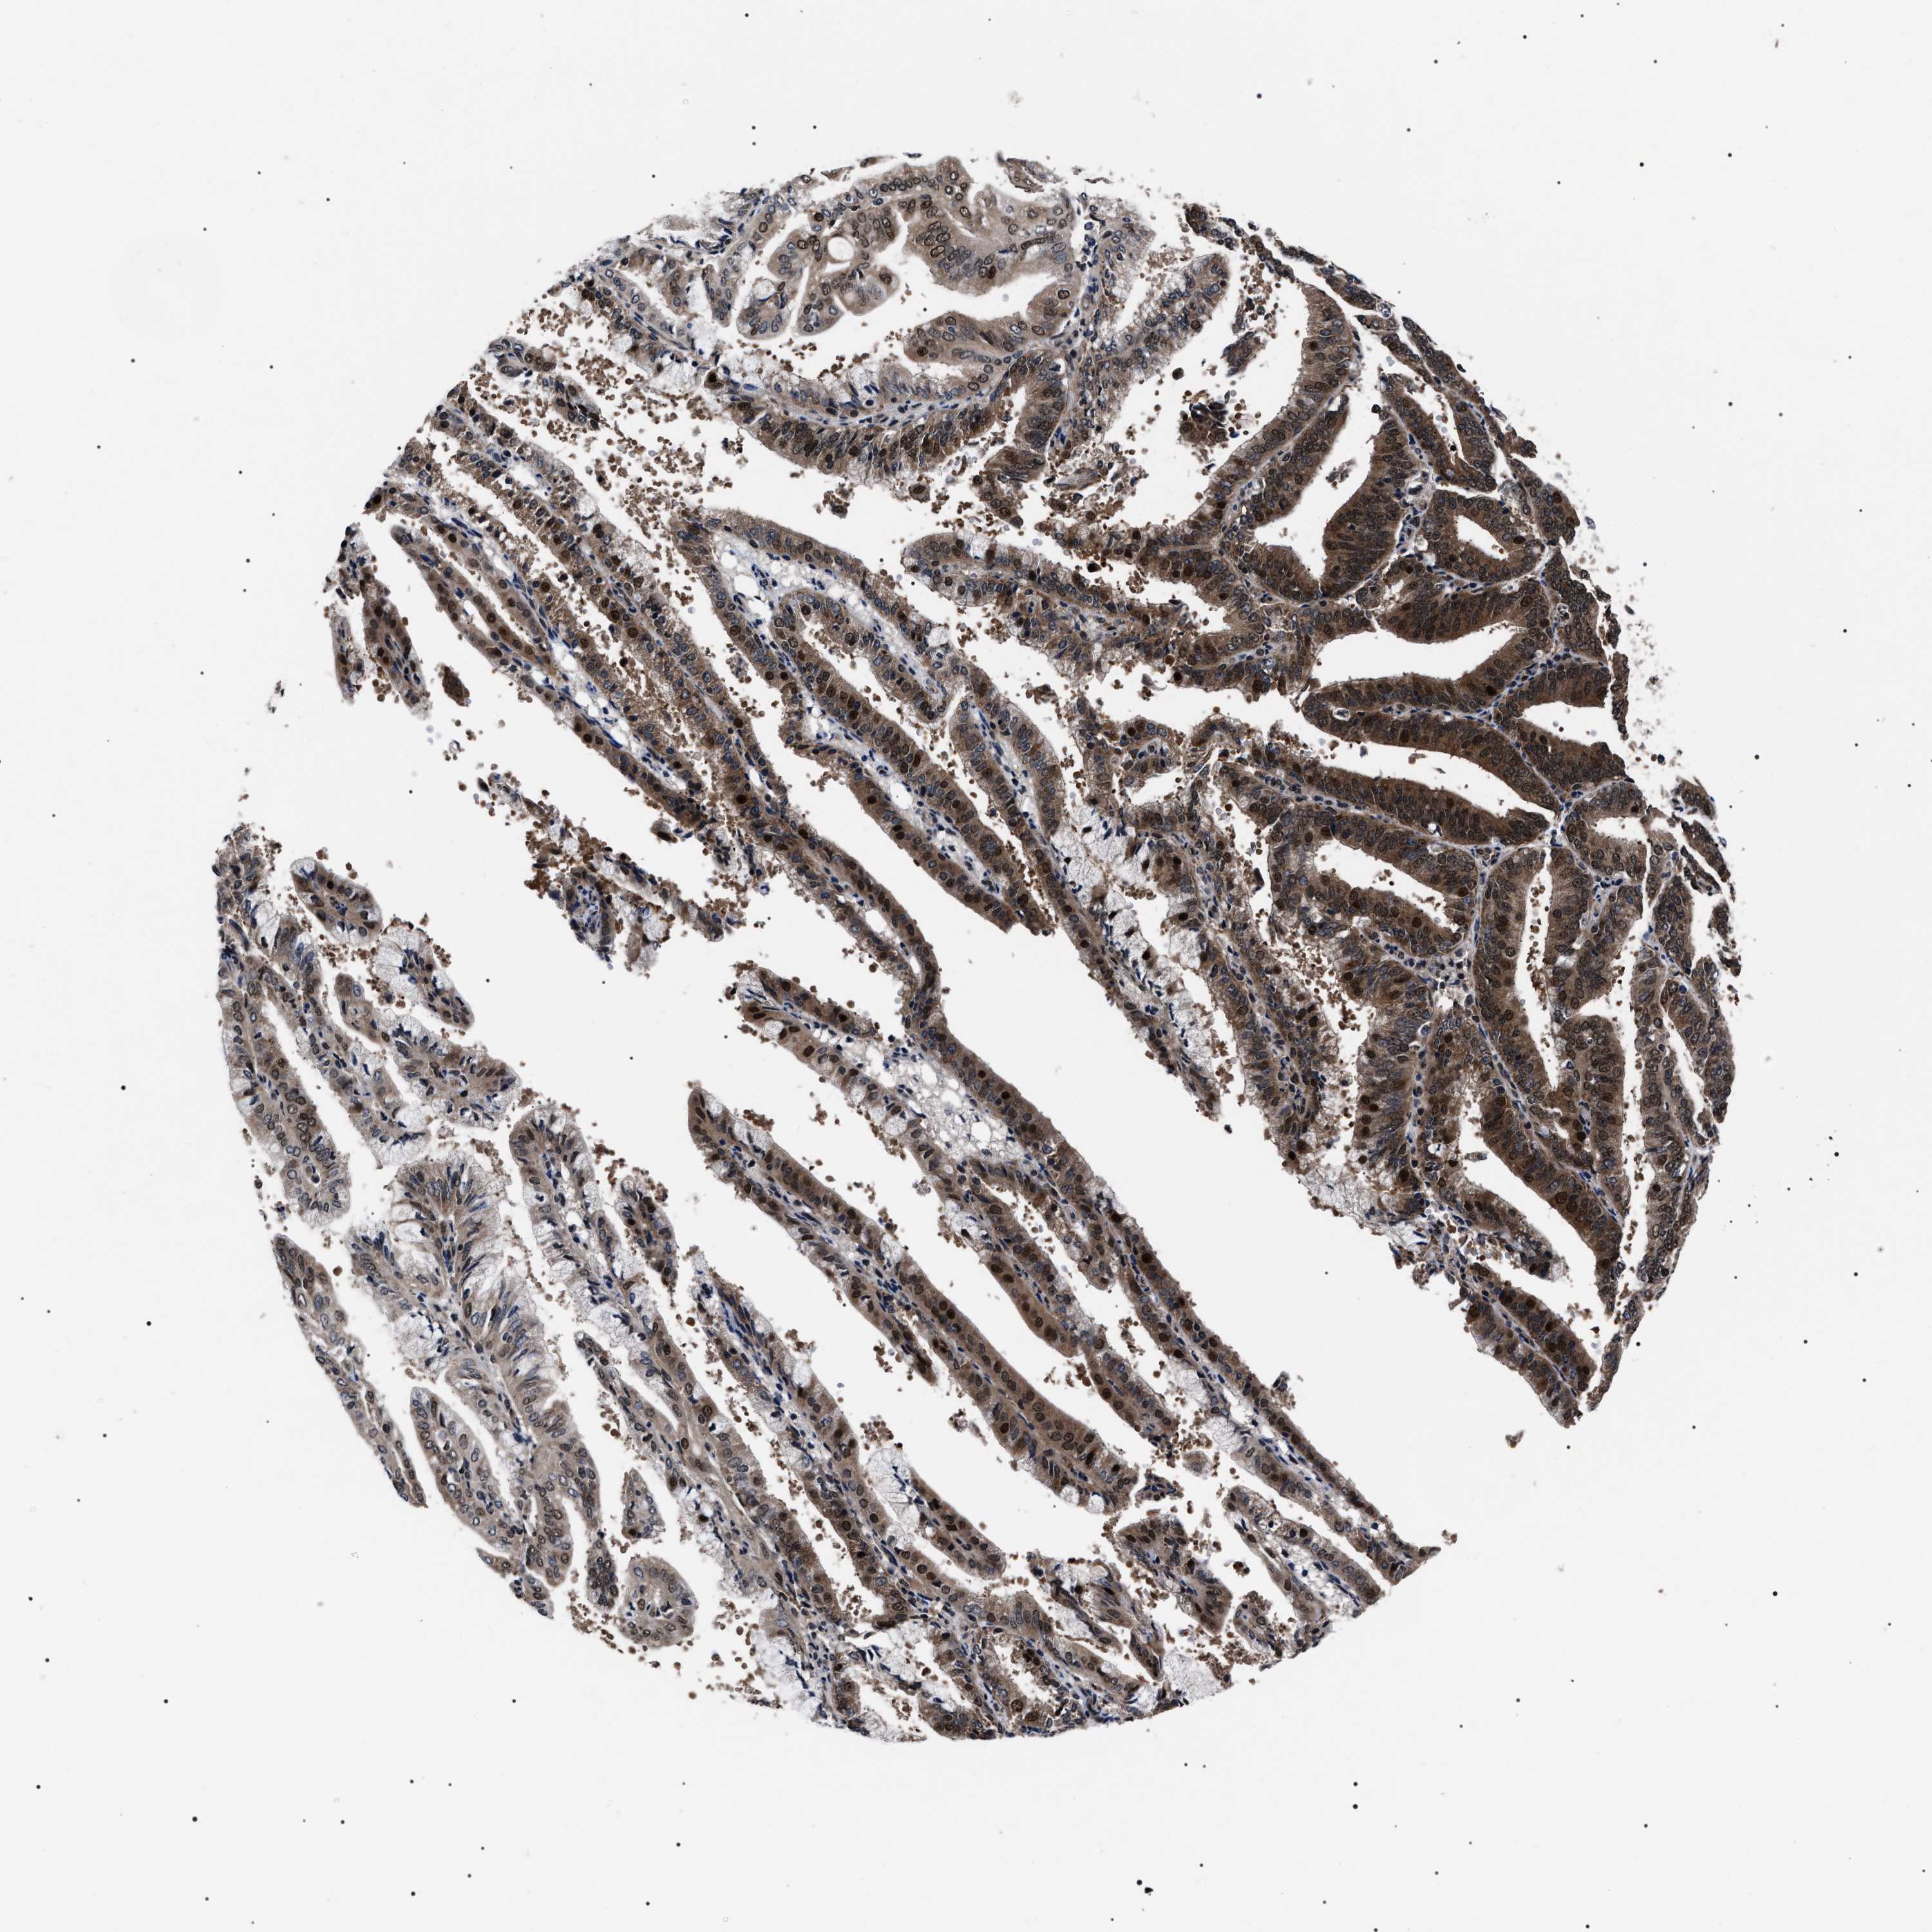

ENDOMETRIAL CANCER - Protein expressioni

A mouse-over function shows sample information and annotation data. Click on an image to view it in a full screen mode. Samples can be filtered based on level of antibody staining by selecting one or several of the following categories: high, medium, low and not detected. The assay and annotation is described here.

Note that samples used for immunohistochemistry by the Human Protein Atlas do not correspond to samples in the TCGA dataset.

Antibody stainingi

Antibody staining in the annotated cell types in the current human tissue is reported as not detected, low, medium, or high, based on conventional immunohistochemistry profiling in selected tissues. This score is based on the combination of the staining intensity and fraction of stained cells.

Each image is clickable and will lead to virtual microscopy that enables deeper exploration of all samples and also displays staining intensity scores, fraction scores and subcellular localization as well as patient and tissue information for each sample.

Antibody HPA061698

Antibody CAB020680

Antibody CAB069395

Staining

High

Medium

Low

Not detected

Intensity

Strong

Moderate

Weak

Negative

Quantity

>75%

75%-25%

<25%

None

Location

Nuclear

Cytoplasmic/membranous

Cytoplasmic/membranous,nuclear

Adenocarcinoma, NOS

Adenocarcinoma, metastatic, NOS